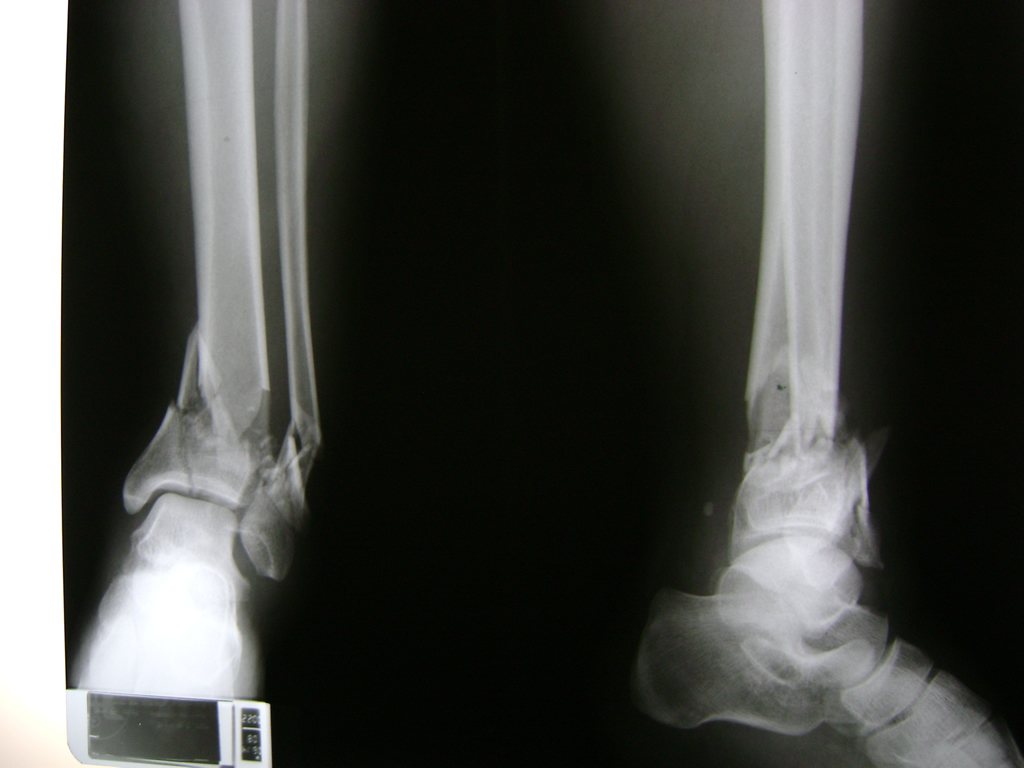

Una fractura de tobillo es la rotura de uno o más de los huesos del tobillo. Estas fracturas pueden ser:

- Completas (el hueso está perforado y está en 2 partes).

- Los extremos de los huesos están desalineados entre sí (desplazados).

- La fractura se extiende hasta la articulación del tobillo (fractura intra-articular).